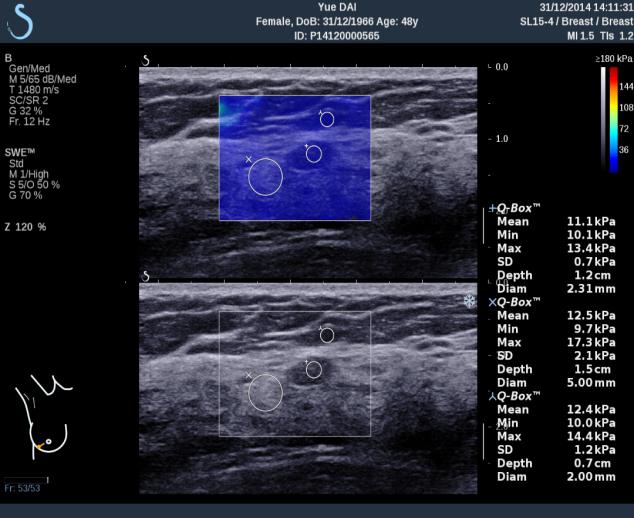

E成像(SWE)實時剪切波彈性成像技術(shù)

“聲藍”獨有的E成像(SWE)實時剪切波彈性成像技術(shù)可以廣泛應(yīng)用在實性臟器腫瘤的早期檢出和鑒別診斷、定量評估、介入穿刺引導(dǎo)、各類疾病治療前后的評價等,也是唯一全面通過美國FDA認證的實時、全幅、全定量的組織硬度可視化測量模式,因而為臨床診斷和治療,提供了安全、無創(chuàng)、有效的最新影像學全新檢查方法。目前已被應(yīng)用于甲狀腺、乳腺、肝臟、腎臟、前列腺、腸管、淋巴結(jié)、肌肉骨骼、軟組織等全身器官的鑒別診斷和定量評估。

彈性超聲與以往普超聲相比,相當于“深觸診”,可以更加直觀地“接觸到”軟組織的形態(tài),并且速度可達到1厘米/秒。與此同時,它的畫面是連續(xù)性的,具有以往單點式的超聲設(shè)備無可比擬的優(yōu)勢。它的“彈性”級別也是最高的,特別適應(yīng)于甲狀腺和乳腺的超聲診斷,并且配備了多個探頭,適用于人體不同部位的超聲需求。彈性超聲的引進與應(yīng)用,可對腫瘤的良惡性鑒別診斷及肝纖維化的無創(chuàng)診斷提供重要依據(jù),可明顯提高診斷準確率,具有非常高的敏感性、特異性,提高檢出率,為臨床診斷及治療提供重要依據(jù),盡早為患者爭取最佳的治療時機。